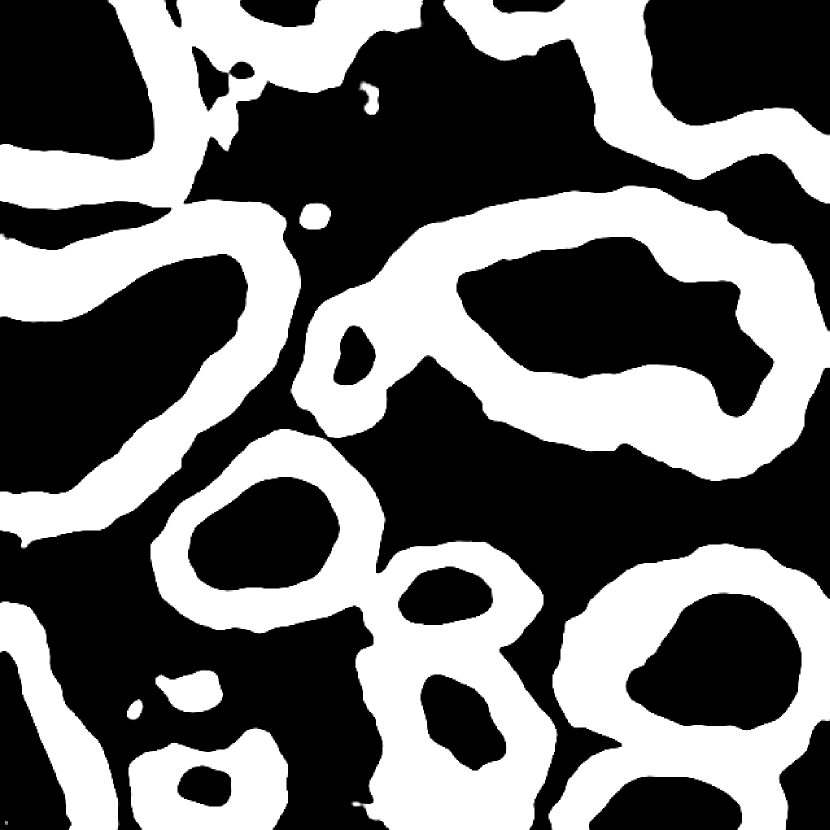

Fig. 3 shows two image examples, their ground-truth masks, and the final segmentations generated by competing models. Comparing with U-Net, Res-Seg based models generally have fewer false positives. Comparing with Res-Seg-Net, Res-Seg-Net and Res-Seg-Net both generate cleaner outputs, which can serve as an evidence that hierarchical refinings are effective in improving segmentations in both accuracy and robustness. These effects can be clearly seen within the areas highlighted with green boxes.

We fed Res-Seg-Net with the patch in the first row of Fig. 3, and output their segmentations maps of each layer in Fig. 4. The segmentation refining process is evident, as more and more details are added to the finer outputs. The low resolution segmentations tend to catch the primary shapes of the target objects. Moving upwards, they not only provide guidance for fine-resolution labelings to capture more details, but also set up certain guard to reduce the appearance of noisy spots.